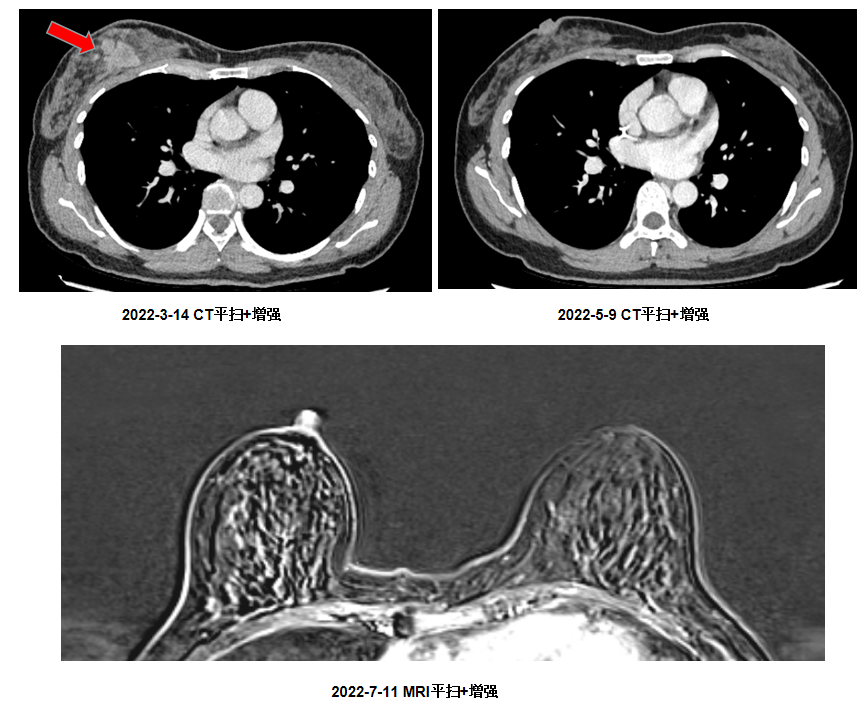

2022-3-14 CT平扫+增强提示:右乳内见一结节状软组织影,大小约2.9×2.9cm,边界毛刺、分叶。

2周期 2022-5-9 CT平扫+增强提示:右乳未见明确肿块影。

6周期 2022-7-11MRI平扫+增强提示:两侧乳腺呈多腺体型,腺体组织呈斑片、斑索状、结节状信号增高影,信号不均匀,边缘模糊;DWI未见弥散受限,两侧乳腺象限未见明确肿块及异常强化征象。两乳皮肤、乳头未见异常。

治疗6周期后,2022-7-11乳腺MRI未见明显肿物,疗效评估CR。